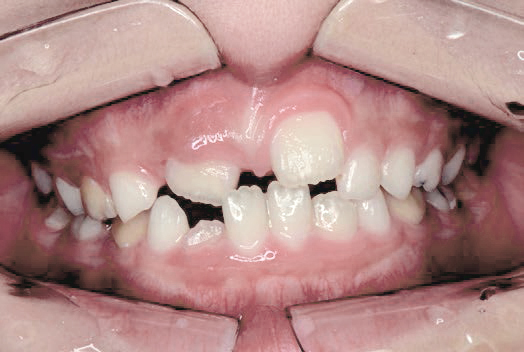

ガタガタな歯並びに悩むも…抜かずに治す選択

Kさん (矯正開始時:8歳)

Before

After

前歯のすき間や歯並びの乱れが見られ、普段の生活の中で、無意識に舌を押しつけるクセや飲み込み方のクセが確認されました。

治療を終えて

装置をしっかり使うことで、あごの位置が整い、舌の正しい位置や動きが戻り、ほっぺたやくちびるの筋肉の使い方も改善されました。その結果、歯並びが整いお口の機能も良くなりました。もちろん非抜歯での治療です。

主訴・治療内容 他院で抜歯のうえ、ブラケット矯正を勧められたが、できれば歯を抜かずに治療したいとの要望で来院されました。

治療期間 5年4ヶ月

費用 495,000円(税込)